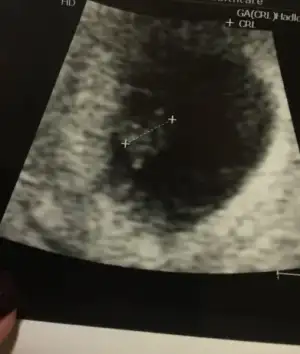

Havalianne__ Havalianne__ bana da bi yorum yaparmısın rica etsem:) çok ortada senin yorumunu merak ediyorum.. Burda 9 haftalık ve karından çekildi